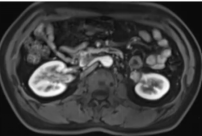

(2)下腹部增强核磁:显示右侧肾盂增厚,输尿管上段周围软组织增厚、管腔狭窄。